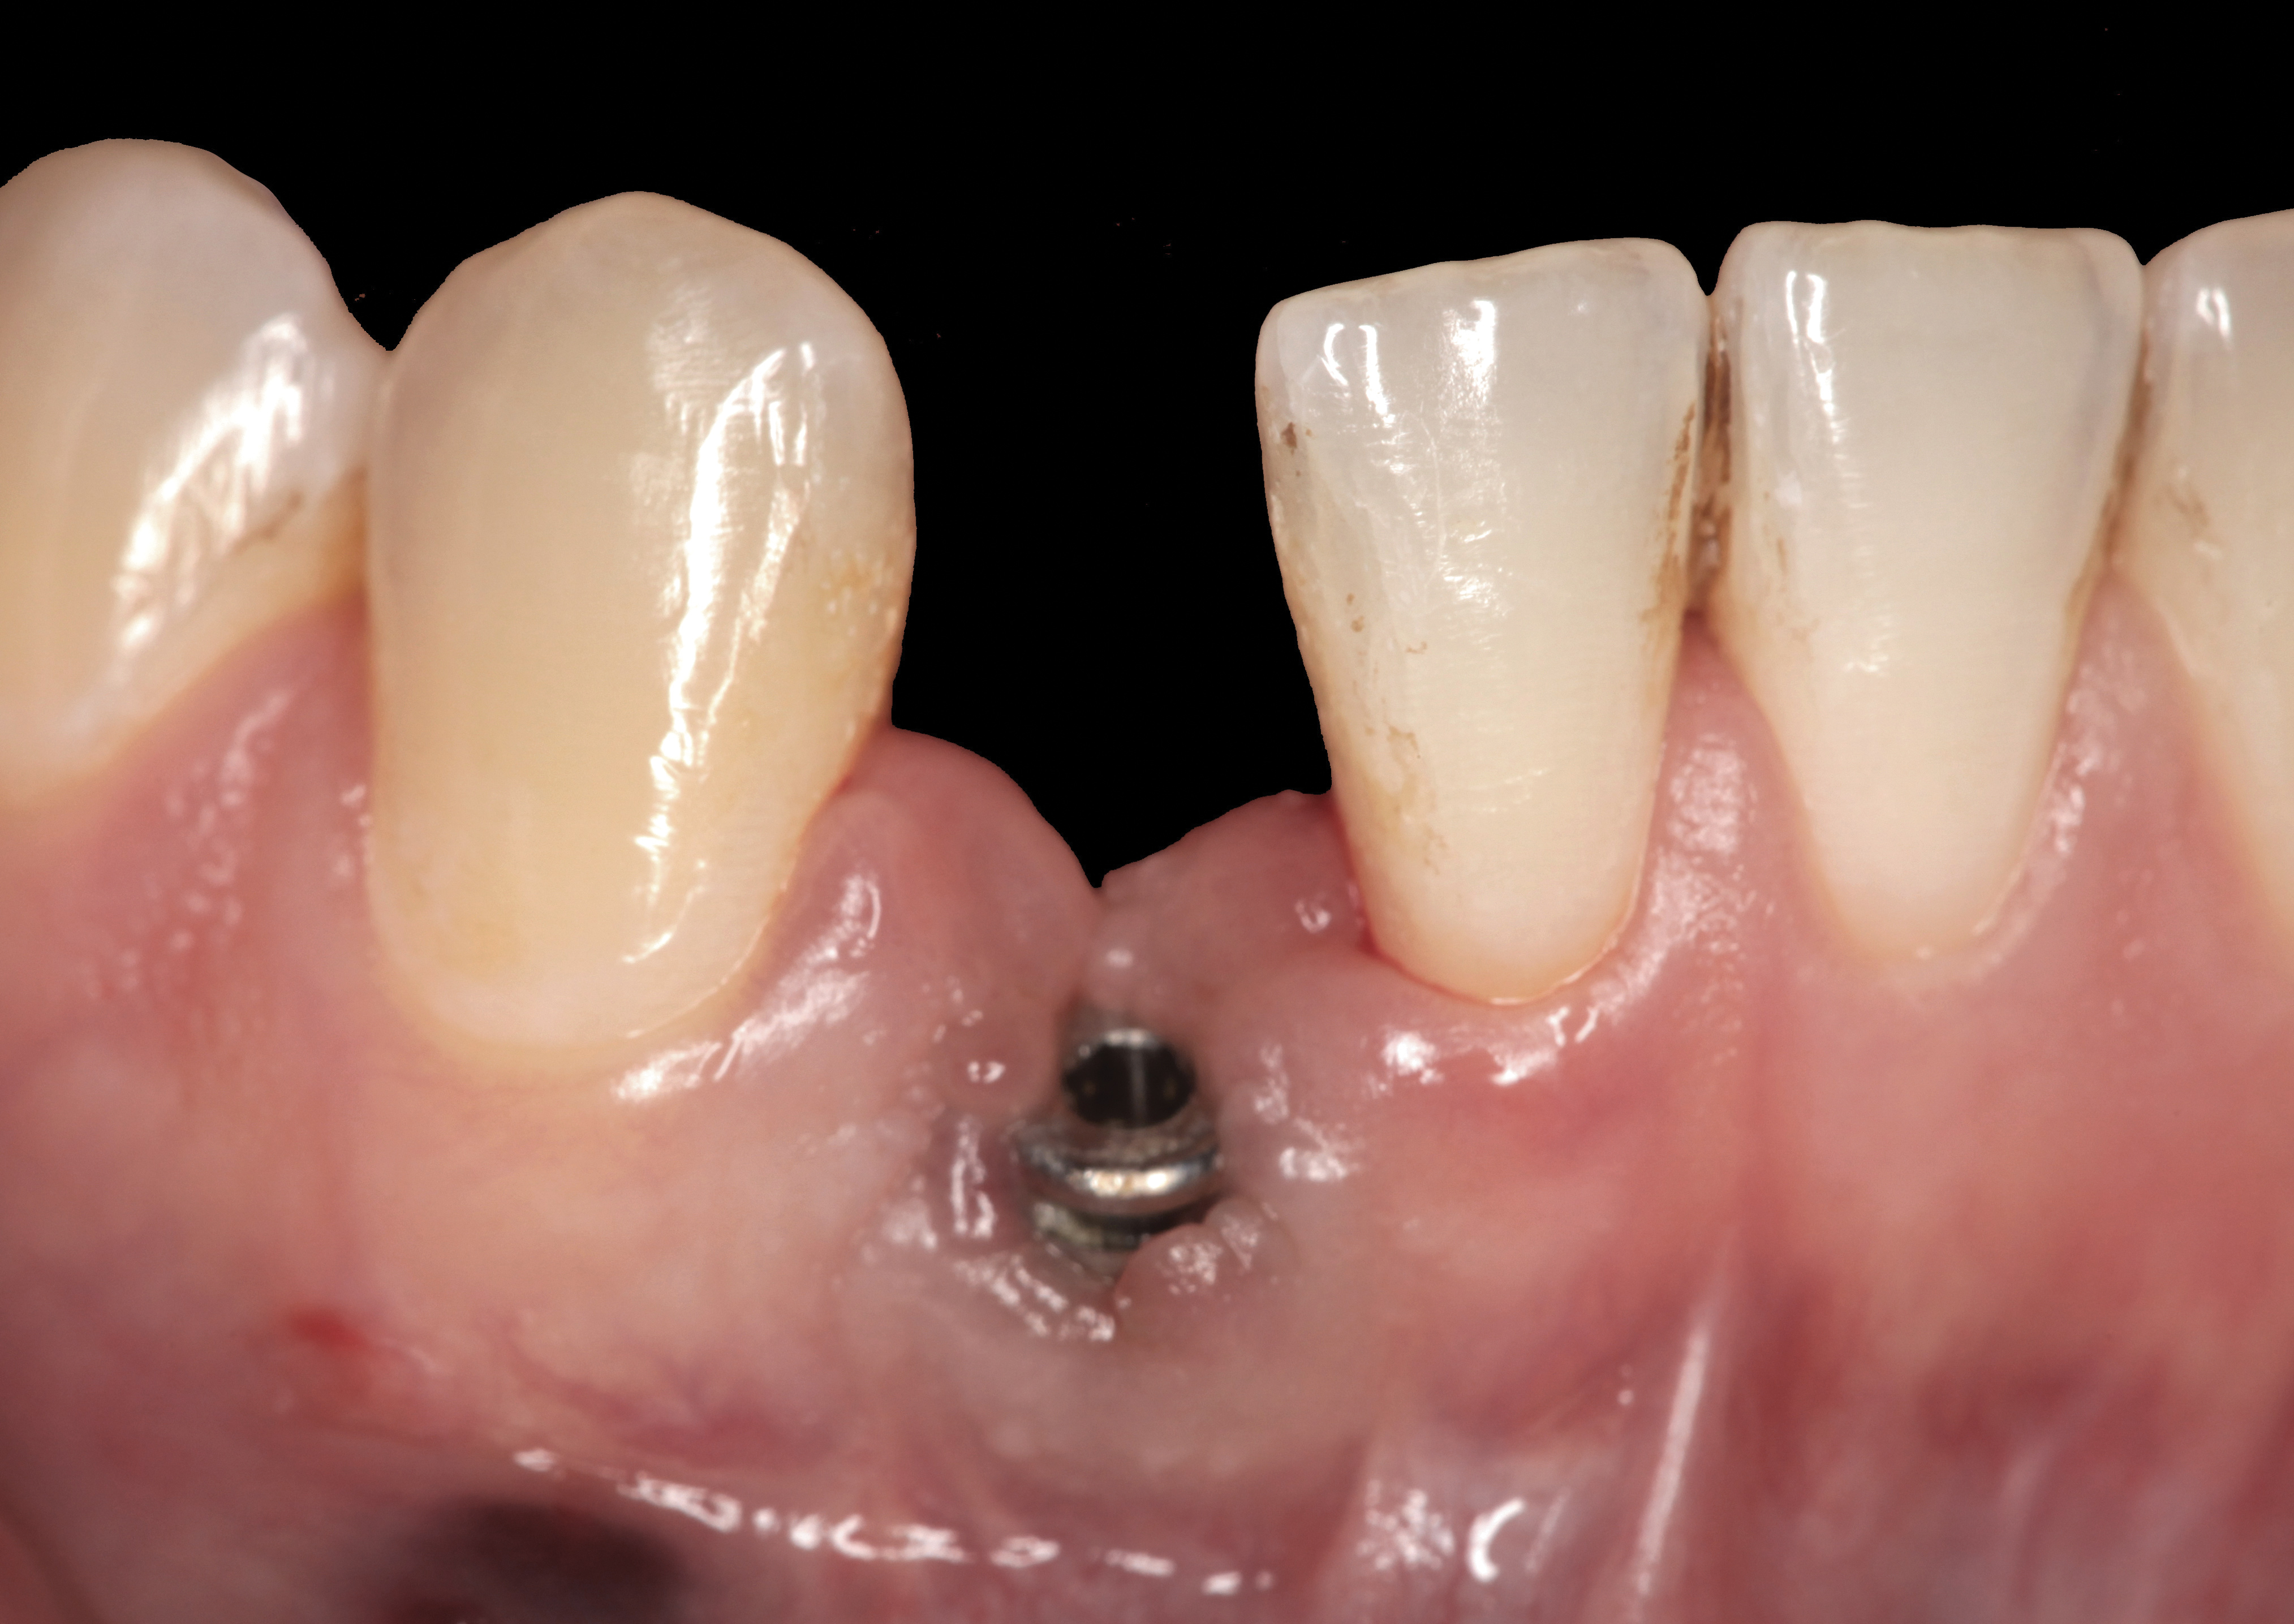

Fig 34. A surgical cover screw was placed in an attempt to decoronate the implant and gain soft-tissue coverage in situ.

Figure 34

The following case report provides an example of this case scenario: A 24-year-old white male presented with congenitally missing tooth No. 26 restored with a single-tooth cement-retained implant restoration. The implant was placed excessively to the facial aspect of the edentulous site and too shallow, and the periodontal phenotype was thin scalloped (Figure 32). In an effort to mimic the lost midfacial soft tissues, pink ceramics were used as a cosmetic facade. Even though the restoration was not in the esthetic zone, the patient was highly displeased with the esthetic outcome and sought remediation.

The crown and screw-retained custom abutment were removed, and a surgical cover screw was placed into the implant, thereby allowing spontaneous gingival augmentation in situ (Figure 33 and Figure 34). Note that the lingual aspect of the implant site was significantly more coronal than the labial aspect, which was positive because the defect would be limited to a facial–lingual defect. A fixed RBR bridge was cemented on the adjacent teeth and used as a tooth-supported transitional provisional restoration (Figure 35). A few weeks were allotted to let the soft tissue heal and migrate around the cover screw (Figure 36) to see if there would be complete coverage, thereby allowing a soft-tissue augmentation procedure to be performed with primary flap closure as in clinical scenario No. 2. The major obstacle in achieving a positive tissue response was that the implant depth was also deficient because the implant–abutment connection was at the level of the free gingival margin. It was decided that the best treatment option would be to remove the implant. A high-powered reverse-torque device (Fixture Remover Kit, NeoBiotech, www.neobiotechus.com) was used to remove the implant atraumatically (Figure 38 through Figure 41). The implant socket was allowed to heal for several months not unlike an extracted tooth (Figure 42). A new implant was placed in a better position from both a restorative and esthetic perspective (Figure 43), and after a few months of healing, a new crown was made (Figure 44). A satisfactory functional and esthetic result was achieved (Figure 45 and Figure 46) without employing pink porcelain.